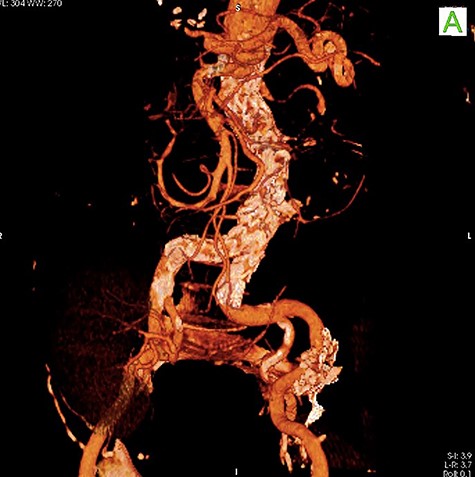

A 59-year-old male presented with end-stage liver disease secondary to hepatitis C and end-stage renal disease. On CT scan, an abdominal aortic aneurysm was incidentally found with a diameter of 4*3.8 cm (Fig. 1).

Given the rapid decompensation in the patient, a simultaneous liver-kidney transplant was proposed, but because the accepted diameter of aneurysm for surgical management is 5.5 cm and higher [1], it was decided to closely follow-up with the patient post-transplantation. The liver was transplanted using the piggy-back technique, inferior vena cava was anastomosed side-to-side, and portal veins and hepatic arteries were anastomosed end-to-end. The donor kidney was placed in the right iliac fossa with anastomosis of the right internal iliac artery and vein in an end-to-end fashion. The patient then had an uncomplicated post-operation course and was discharged with an immunosuppressive regimen. One month later, the patient came to the emergency room with severe abdominal pain. To rule out possible aneurysm rupture, an emergent CT scan with contrast was performed; however, the findings were compatible with an infrarenal aortic aneurysm with eccentric mural thrombosis. In addition, the aneurysm had grown in size and had a diameter of 5.2*6.5 (Fig. 2).